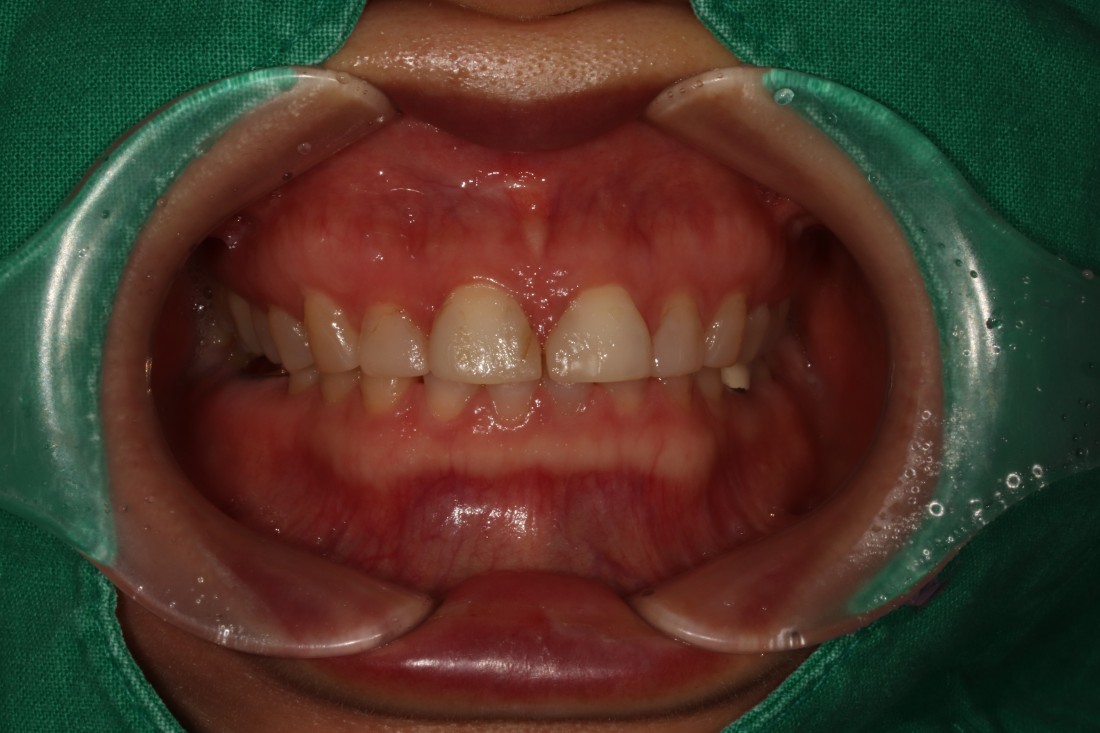

그렇지만 실제로 라미네이트 전/후 사례를

200케이스 가까이 공유하는

라미네이트 치과를 찾기는

쉽지 않은데요.

광주 무삭제 라미네이트 치과는

벌어진 앞니 / 깨진 앞니 /

얼룩덜룩한 앞니 / 왜소치 등

다양한 사례의 라미네이트 전-후 사진을

투명하게 공개하고 있습니다.